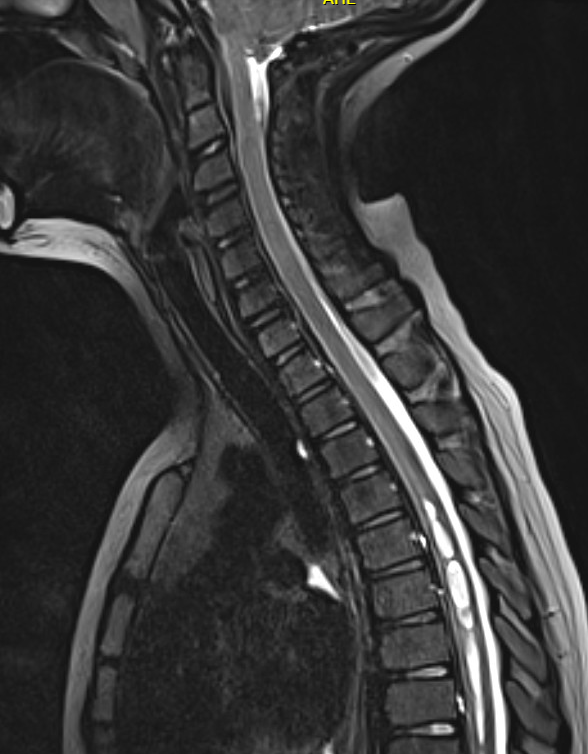

Here is an image of the spine from a year ago, showing syringomyelia, which has been unchanged for several years.